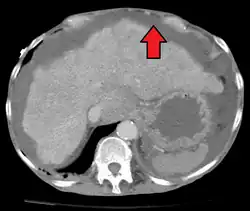

| Diagnostic method | Physical exam, ultrasound, CT scan[3] |

In the developed world, the most common cause is liver cirrhosis.[4] Other causes include cancer, heart failure, tuberculosis, pancreatitis, and blockage of the hepatic vein.[4] In cirrhosis, the underlying mechanism involves high blood pressure in the portal system and dysfunction of blood vessels.[4] Diagnosis is typically based on an examination together with ultrasound or a CT scan.[3] Testing the fluid can help in determining the underlying cause.[3]

Ultrasound investigation is often done before attempts to remove fluid from the abdomen. This may reveal the size and shape of the abdominal organs, and Doppler studies may show the direction of flow in the portal vein, as well as detecting Budd–Chiari syndrome (thrombosis of the hepatic vein) and portal vein thrombosis. The sonographer also can estimate the amount of ascitic fluid, and difficult-to-drain ascites may be drained under ultrasound guidance. An abdominal CT scan is more accurate than a sonogram to reveal abdominal organ structure and morphology.[13]